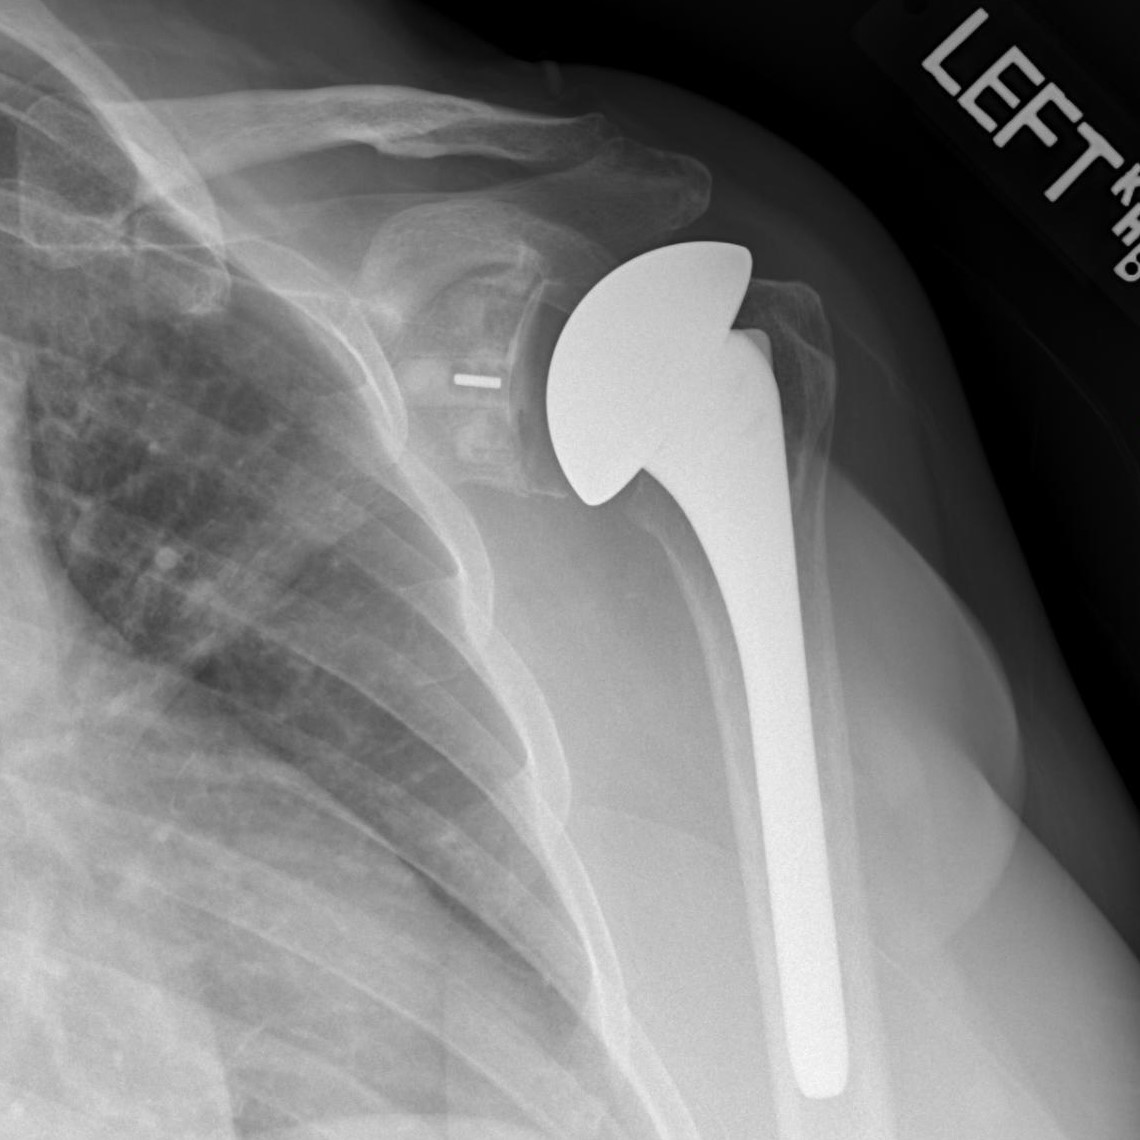

Рентген плеча: примеры снимков и их расшифровка